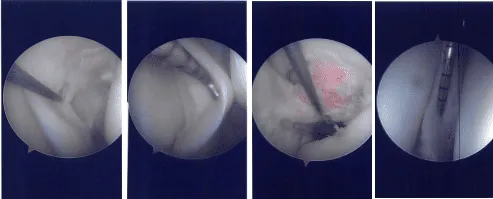

Intraoperative Arthroscopy Images

Esmarch was applied and the tourniquet was inflated to 300 mmHg. Patellofemoral joint was found to be in good shape with no cartilage damage. The scope was taken to the medial gutter where there was a synovial flap. Medial compartment showed a ramp lesion of the posterior body of the medial meniscus.

Probe was inserted and meniscus tear was again checked. It involved the posterior body of the medial meniscus along the capsule. The decision was made to repair the ramp lesion using all-inside suture configuration using FasT-Fix.

Two curved and two reverse curved FasT-Fixes were used to complete the repair after the meniscus was abraded along with a capsule abrasion done with the shaver. The repair was found to be in good position.

Now the scope was moved to the internal trochlear area where ACL was deficient. Debridement was done. The scope was moved to the lateral compartment where we found medial edge fraying as well as a small bucket handle tear of the medial edge of the lateral meniscus.

Further examination showed a horizontal tear going up to the periphery of the lateral meniscus of the posterior body. Three FasT-Fixes were used for repair of the lateral meniscus, horizontal lesion.

Sims speculum was inserted to protect the posterior neurovascular bundles. After it was done, the scope was reentered and the repair of the left meniscus using FasT-Fixes were done in a satisfactory fashion. Microfracture of the trochlear notch was performed using bundle fix.

The tourniquet was released, and bleeding bone could be seen from the microfracture site. The posterolateral wound Incision was washed and closed. Hemostasis was achieved. Closure was done in layers. The posterolateral incision was closed with Monocryl. The arthroscopic portals were closed using nylon.